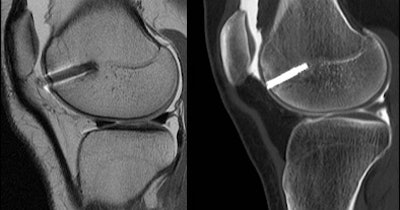

And in a patient who had undergone both CT and MR arthrography, MDCT clearly showed the placement of a screw in the femur with respect to the articular surface and the patellofemoral joint, Gold said. The exact placement of the screw could not be determined in a corresponding MRI image acquired concurrently. In this case, he said, the CT image convinced the surgeon that further intervention was unnecessary.

![]() |

| CT arthrogram (right) shows placement of screw in the femur with respect to the articular surface and the patellofemoral joint. On MRI (left) the location of the screw relative to the bony cortex is difficult to pinpoint due to surrounding artifact. |